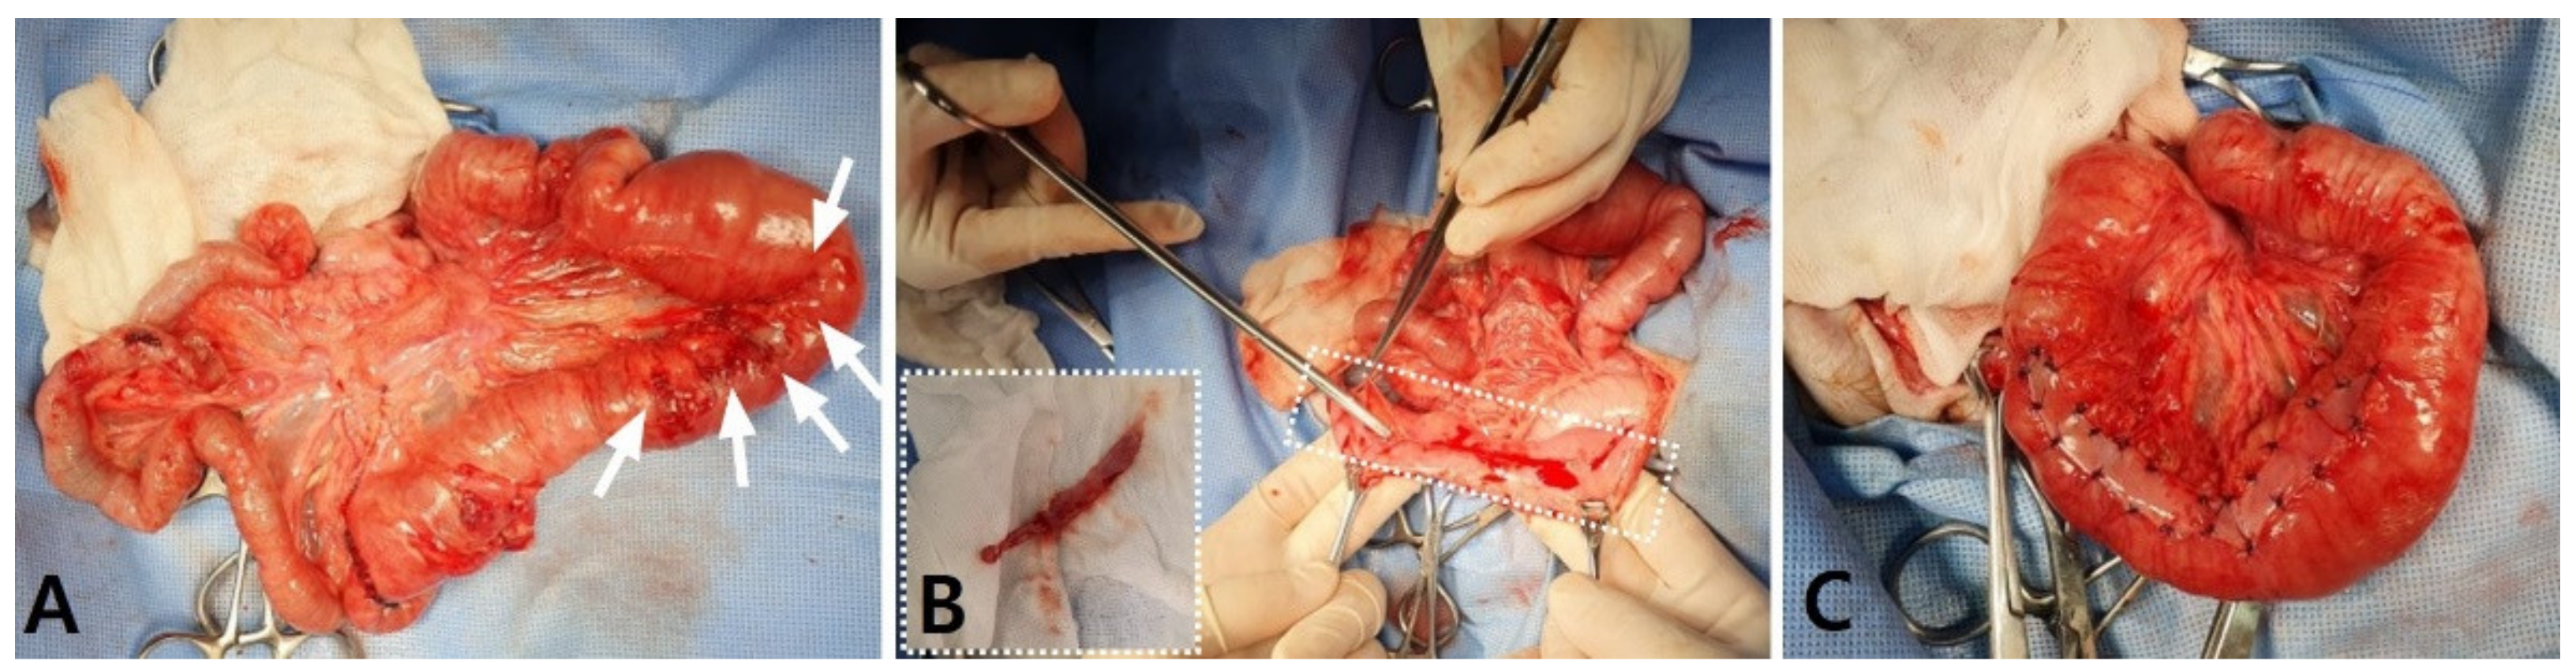

A physical examination on presentation revealed decreased appetite, depressed mentation, mild abdominal pain on palpation, hyperthermia (39.8 °C), and 8% dehydration. The dog’s perfusion parameters were within the normal limits. Hematology revealed normocytic normochromic anemia (packed cell volume (PCV), 28.3%; reference range, 37–55%), leukocytosis (28.83 × 109/L; reference range, 6.0–17.0 × 109/L), and neutrophilia (24.36 × 109/L; reference range, 3.0–11.5 × 109/L), with some toxic changes and reactive lymphocytes. A biochemical analysis, gas analysis, and coagulation test revealed no abnormalities except the elevated C-reactive protein (CRP) level (3.6 mg/dL; reference range, <1.0 mg/dL). Abdominal radiography revealed loss of serosal detail and small-intestinal dilation, with the ratio between the maximal small-intestine (SI) diameter and the height of the fifth lumbar vertebral body (L5) increasing to 2.24. Abdominal ultrasonography revealed a severe dilation with intraluminal intestinal contents and accumulation of fluid in almost the whole jejunal segment, with its largest diameter being 18 mm, as well as jejunal lymph node enlargement. Markedly reduced gastrointestinal motility was generally shown, but remarkable pathological changes were not identified in other gastrointestinal segments except for the jejunum. No foreign material was identified in any segment. A small amount of peritoneal effusion around the urinary bladder and mild hyperechoic change in the mesentery were thought to be due to the previous operation. To identify the cause of the severe jejunal dilatation and the presence and level of the obstacle, a CT scan (LightSpeed; GE Medical System, Milwaukee, WI, USA) was obtained under general anesthesia. The imaging protocols were 120 kVp, 200 mAs, 512 × 512 matrix, and 0.6 rotation time with a 1.25 mm slice thickness. For a contrasting CT examination after the plain CT scan, iohexol (Omnihexol 300; Korea United Pharmaceutical, Seoul, Korea) was manually injected at 600 mg iodine/kg into the cephalic vein. All CT images were transferred to a workstation using a commercially available DICOM imaging analysis software (Osirix viewer; Pixmeo, Los Angeles, CA, USA). The abdominal CT scan revealed generalized gastrointestinal dilatation with abrupt narrowing of the jejunal segment and SBFS (Figure 1). The small intestines were plicated and tortuous, and the jejunal segment was abruptly narrowed to a 4.0 mm diameter. The stomach, duodenum, and jejunal loop proximal to the narrowed lesion were moderately to severely dilated, representing a jejunum with a 21.9 mm maximal diameter. The jejunum distal to the narrowed lesion was normally to mildly dilated, within 8.7 mm in diameter. An SBFS consisting of intraluminal particulate-like materials mixed with gas bubbles was observed within the dilated jejunal segments distal to the narrowed lesion and entire ileum. The lumen of the dilated stomach contained food residues, but there were no remarkable changes in wall thickness or patency. The large intestines, including the cecum, colon, and rectum, were collapsed without fecal contents. A small quantity of free fluid around the dilated jejunal segment and a diffusely hyper-attenuated mesentery were identified. On the basis of the imaging findings, the dog was diagnosed as having SBO of the jejunal segment caused by the stenotic jejunal lumen. The SBO was estimated to be of high grade, with >50% discrepancy between the proximal and distal small-bowel luminal calibers based on the previously reported human classification system [9]. No causes that could induce SBO, such as foreign bodies or other intestinal wall abnormalities, were identified.

Figure 1. Postcontrast dorsal (A,E), transverse (B,C), and sagittal (D) computed tomography images of the abdomen of the dog with severe dilatation of the overall small intestines. The stomach and overall jejuna are markedly dilatated, and the proximal jejuna are plicated at an acute angle, causing a stenotic lumen (B, black arrowhead). The small-bowel fecal signs show hyper-attenuated fecal-like materials mixed with gas bubbles from the dilated jejunal segments to the entire ileum (A,C,D, white arrows). The large intestines from the ileocecocolic junction to the rectum are collapsed, with little gas and no fecal contents (CE, black arrows).